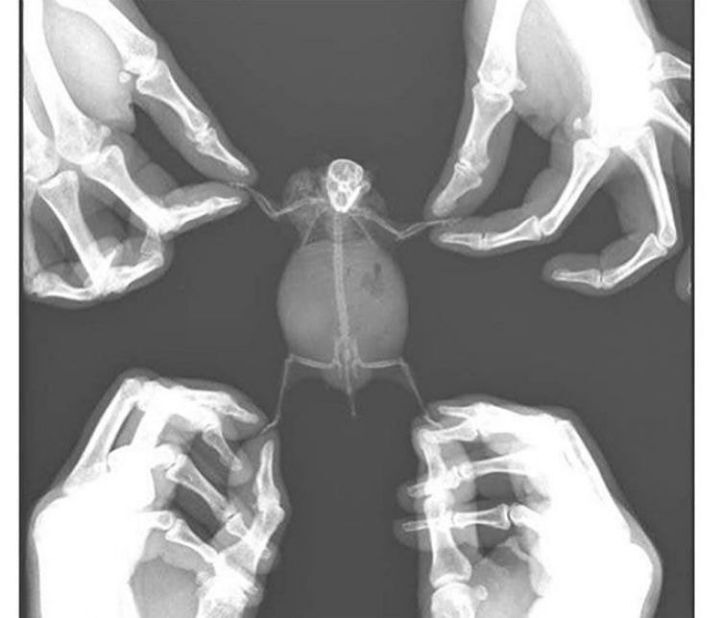

다른 햄들 엑스레이 사진 주운거